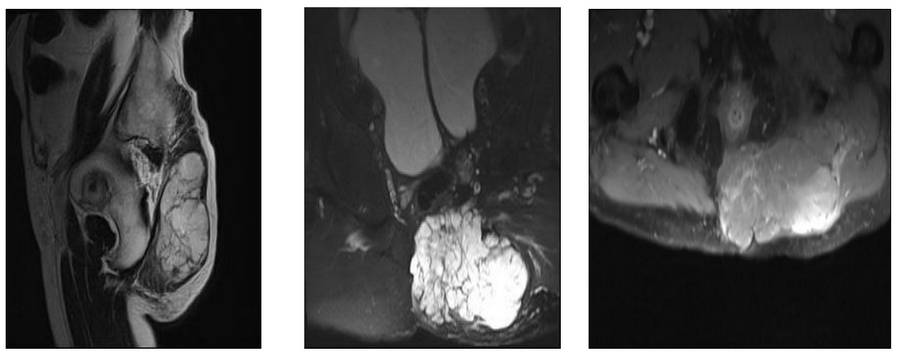

Before surgery: The MRI shows a large tumor with irregular borders extending into the muscle.